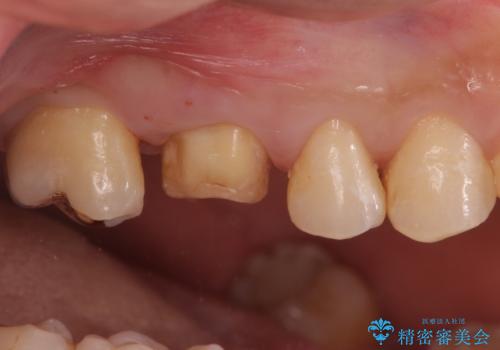

不適な樹脂の詰め物 被せ物で被覆

- 奥歯の劣化・変色した樹脂の詰め物をやり直していきます。

セラミックのインレーでは強度に不安が残るため、セラミッククラウンで全体を被覆することとしました。

- 右上6:仮歯+ジルコニアクラウン/11,000円+110,000円費用は治療当時の料金となります